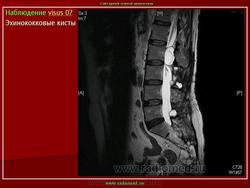

Магнитно - резонанснуютомография применяли на завершающем этапе неинвазивного диагностического обследования 13 больным эхинококкозом печени с целью детализации характера патоморфологических изменений в очаге поражения и уточнения степени вовлечения в процесс крупных сосудисто-секреторных структур.

Свободный выбор плоскостей изображения позволил уточнить топический диагноз. С другой стороны, благодаря высокому мягкотканному контрасту при МРТ выявили значимые дополнительные признаки паразитарных кист. Так, например, МРТ была наиболее информативной в выявлении неровностей внутреннего края кисты и начинающегося расслоения паразитарных мембран.

Несомненным преимуществом метода явилась возможность дифференцирования изменений в архитектонике печени с высокой разрешающей способностью. Вокруг гидатидных кист на МР -томограммах визуализировался ободок слабого изменения МР-сигнала (гипоинтенсивный на Т1 ВИ, гиперинтенсивный на Т2 ВИ) с нечеткими контурами, соответствующий перикистозным изменениям (рис 5а,б ). С помощью МР-волюметрии рассчитывали объем эхинококковых кист, объем непораженной паренхимы печени и степень выраженности компенсаторной гипертрофии органа. МРТ позволила диагностировать эхинококковые кисты в брюшной полости при сочетанном эхинококкозе без дополнительного контрастирования кишечника. При проведении МРТ были выявлены